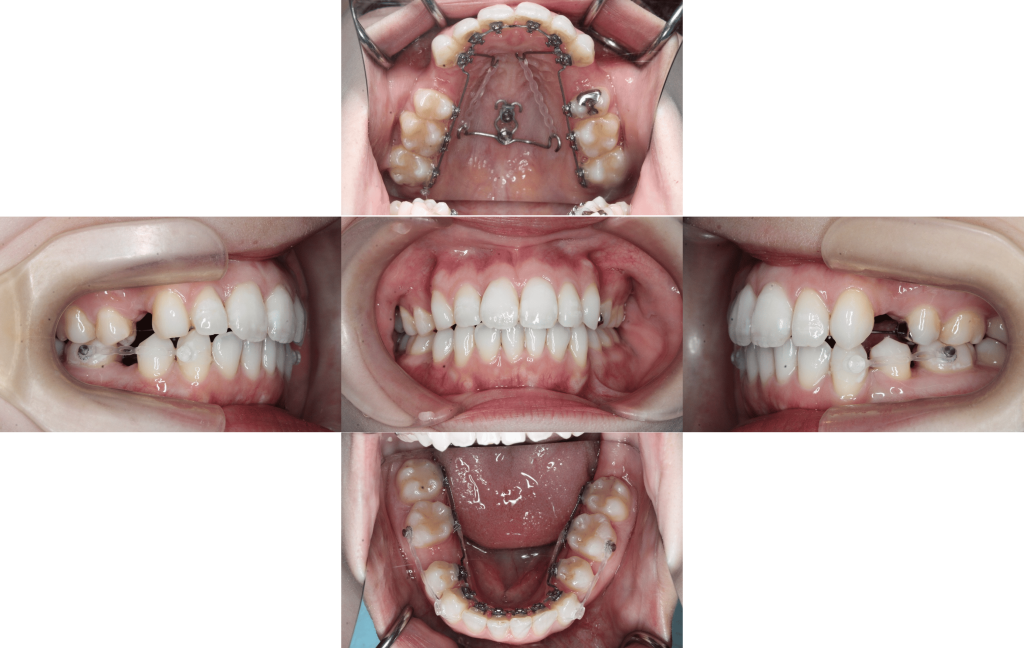

約10か月経過